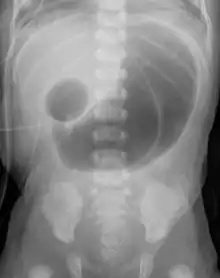

التشخيص